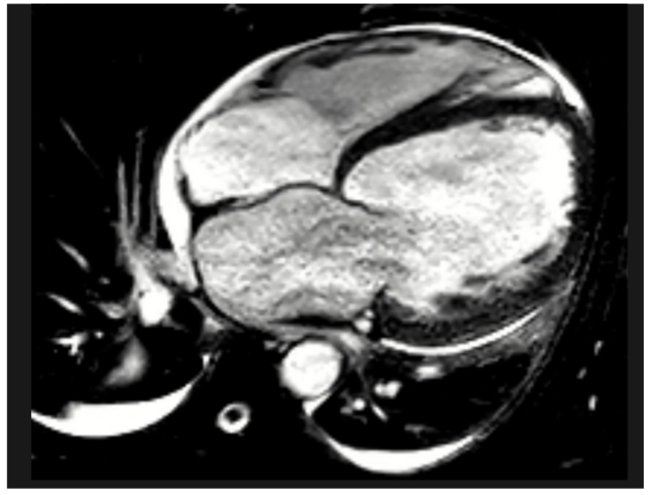

Video 1. Cardiac magnetic resonance imaging showing severe biventricular systolic dysfunction.

(1) Traube’s pulse, also known as pulsus alternans1, was noted on the arterial (Figure 1, red), and pulmonary artery waveforms (Figure 1, yellow), corresponding to severely impaired bi-ventricular systolic function (Video 1). There are two proposed mechanisms for Traube’s pulse. The first mechanism involves the Frank-Starling relationship, whereby beat-to-beat variations in end-systolic and end-diastolic volume result in variation of the contractile force generated. The second mechanism relates to abnormal intracellular calcium handling resulting in fluctuations in myocardial contractile force, and therefore, forward stroke volume.